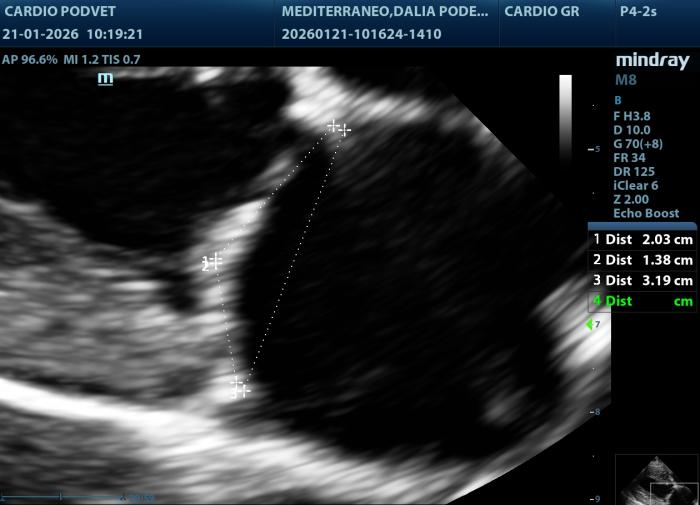

Se han utilizado medidas ecocardiográficas ya publicadas anteriormente. El leaflet-annulus indexx (LAI)es un parámetro para evaluar si existe un ensanchamiento del anillo mitral, se realiza mediante la medición de las valvas anterior (AML) y posterior mitral (PML), además del diámetro antero-posterior del anillo mitral (APL), en la vista paraesternal derecha 4 cámaras en la telesístole cardíaca (Figura 1).

Posteriormente se obtiene este índice mediante la siguiente fórmula: LAI= AML (mm) + PML (mm)]/APL(mm). El área mitral se calcula obteniendo los diámetros de la válvula mitral (AM) en la vista paraesternal derecha transversal a la altura de la válvula mitral, con los diámetros anteroposterior (dAP) y diámetro transcversal (dT) (Figura2) y la fórmula: AM = (π x (dAP/2) x (dT/2))/100. Y por último los diámetros y áreas de las valvas mitrales medidas en la vista paraesternal derecha 4 cámaras durante la diástole (Figura3A-B).